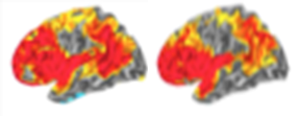

Increasing gyrification in a network of regions in the human brain’s outer mantle is significantly associated with general cognitive ability, a finding replicated in 440 healthy adults and in an independent sample of 662 healthy children who underwent structural MRI scans and extensive neuropsychological testing. The cortex maps showing networks in which gyrification correlates with intelligence are remarkably similar across the two groups. The relationship was also consistent across sexes, the age span, and different methods of estimating intelligence.

Composite MRI data showing brain areas correlated with intelligence were remarkably similar in large independent samples of adults (left) and children (right). Red indicates a stronger connection.